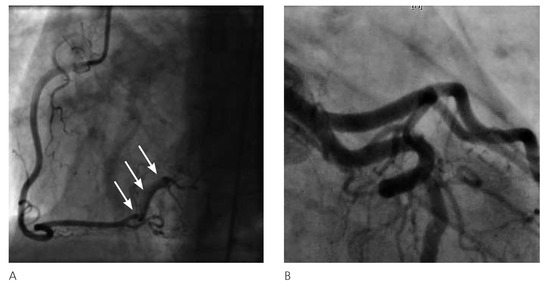

The fact that non-valvular (non-rheumatic) atrial fibrillation creates detectable thrombi in 17% of patients without oral anticoagulation and that 16% of the 17% (over 90% relatively) reside in the left atrial appendage (LAA), suggest that patients w...